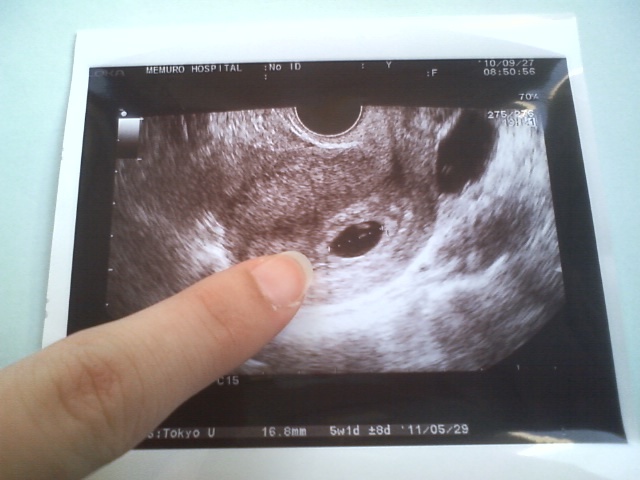

前回は初めての妊娠でお医者さんに

【子宮外妊娠かもしれない】といわれ

とっても不安でみなさんに励ましのお言葉をたくさんいただきとっても励まされました泣き顔

このたび検診でやっと

【正常妊娠・心拍】が確認できました泣き顔